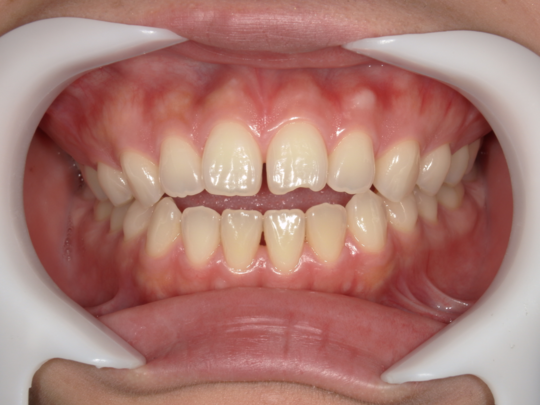

治療後

治療の副作用(リスク)歯の動き方には個人差があり、予想された治療期間が延長する可能性があります。。マウスピースの使用状況、矯正歯科治療には患者さんの協力が必要であり、それらが治療結果や治療期間に影響します